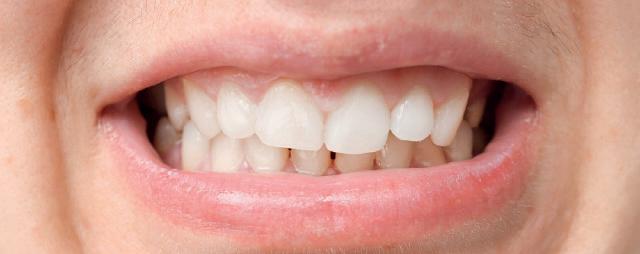

material matters

To use clear aligners to their greatest potential, it’s important to look briefly at their treatment ceiling. Complex cases that include severe bite issues, large gaps, or severe crowding may make this form of treatment less suitable, instead requiring traditional fixed braces. The literature has also cited distalisation, rotation and extrusion as some of the more difficult movements to carry out successfully with clear aligners, and whilst it is not impossible to achieve these results, a relevant case may prompt the need for an alternative treatment approach.

However, recent developments in the materials used to create clear aligners as well as clinical approaches have improved predictability in a wider range of cases.

Polyethylene terephthalate glycol (PETG) materials have been the solution of choice for many complex designs due to their durability, high impact strength and resistance to chemical changes. With impressive mechanical and optical properties, it’s easy to see why they are increasingly preferred.

The future of complex clear aligner cases could lie in shape memory polymers (SMPs), sometimes known as actively moving polymers. This material offers the ability to revert to an original shape when achieving a necessary transitionary trigger, such as a certain temperature for a designated time period. During a treatment cycle, the SMP-based aligner could be subjected to such a trigger, reverting to a predefined shape, and in turn generating forces which can produce orthodontic tooth movement. When designed to harbour multiple aligner shapes within its form, it could reduce the number of aligners used during orthodontic treatment and achieve complex corrections sooner.

Step by step

When tackling a complex case suitable for aligner therapy, treatment is most effective when the dentist creates an efficient and actionable treatment plan. Therefore, one of the most important skills for a clinician providing clear aligners for complex cases is an understanding of how to implement staging.

Those that have prior experience in orthodontics may know that staging refers to the breakdown of an intended movement of teeth in a sequential manner, with the use of aligners. This segmented approach

allows for the close control over linear and rotational movements over time, with each new aligner achieving a specific step that gets a patient closer to their end goal. In complex cases, staging orthodontic tooth movement is essential and can be used to attain better treatment outcomes.

When used in the treatment of severe crowding, staging has provided no significant differences in results when compared to fixed brace treatments, including in case duration. One 2022 study broke up the process into three overarching stages of ‘decrowding‘, ‘space closure’ and ‘fine-tuning’. This allows for targeted movement of the crowded anterior teeth, before achieving a class I canine and molar relationship, and making final adjustments, such as overcorrections – recommended by many in case of possible relapses – and closures of any residual spaces.